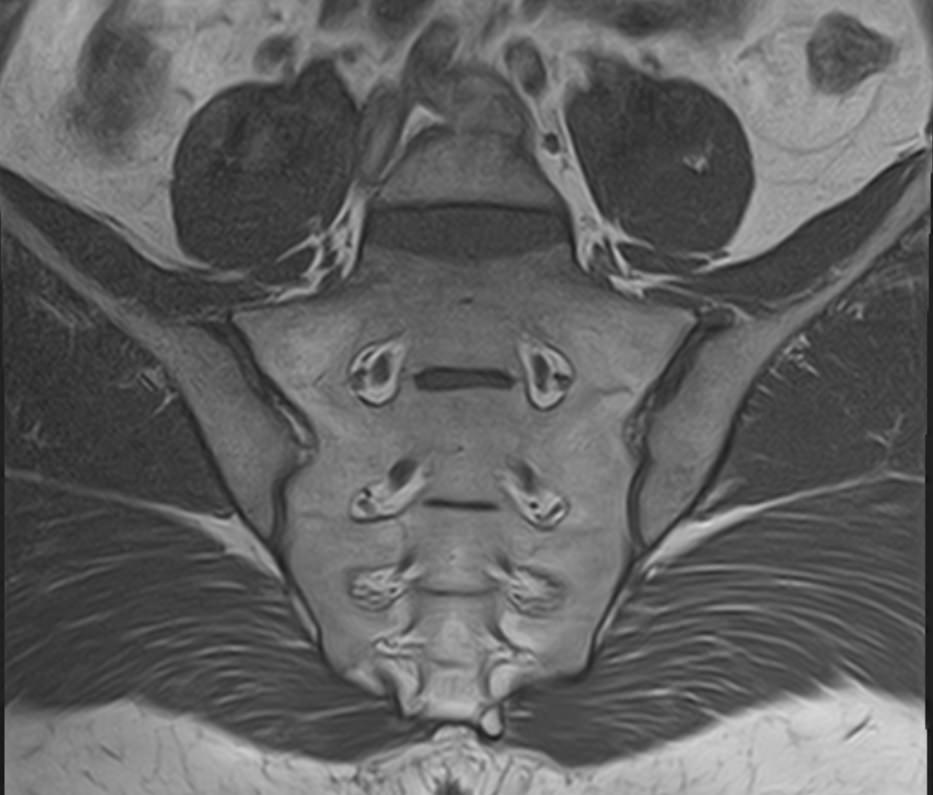

Пояснично-крестцовый отдел позвоночника принимает на себя основной вес тела, поэтому поясничные позвонки отличаются массивным строением. Крестец образует единую кость за счет 5 сросшихся между собой позвонков и помогает поддерживать тело в вертикальном положении. Крестцово-подвздошное сочленение – крупный малоподвижный сустав, место соединения крестца и подвздошных костей. Эти анатомические области испытывают большие нагрузки и достаточно часто вовлекаются в патологический процесс при травмах, дегенеративных поражениях, инфекциях и опухолевых заболеваниях.

Наиболее точным и эффективным способом диагностики причин появления болей в нижней части спины является МРТ. С помощью данного метода можно оценить состояние всех анатомических структур позвоночного столба на исследуемом уровне, диагностировать поражение позвоночника на начальной стадии, когда другие методы не дают результатов. Такой патологией, в частности, является сакроилеит (воспаление крестцово-подвздошного сочленения), который часто становится причиной анкилоза (сращения) или нестабильности (патологической подвижности) сустава. Выявление сакроилеита на ранней стадии значительно улучшает прогноз в плане лечения и профилактики осложнений.

Что можно диагностировать при проведении МРТ пояснично-крестцового отдела позвоночника + МРТ крестцово-подвздошных сочленений

При проведении данного комплексного обследования можно выявить:

• спондилиты, гнойные артриты, сакроилеит, абсцессы околопозвоночных тканей и другие воспалительные заболевания, туберкулез;